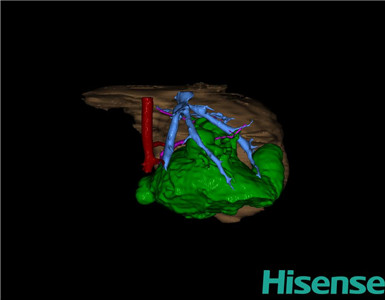

CT结果输入海信CAS系统后行3D重建及手术规划后,于2015-9-14全麻下行“胆总管囊肿切除+胆囊切除+胆总管-空肠吻合术”手术治疗:

术前三维重建及手术方案设计:

将0.625mm双源薄层CT资料的静脉期和动脉期Dicom格式文件导入海信CAS系统。

通过调节窗宽窗位调整CT序号,对肝实质,胆囊,下腔静脉,肿瘤,肝动脉、门静脉及肝静脉等进行三维重建;系统自动计算肝脏体积。

术前三维重建:

重建图片